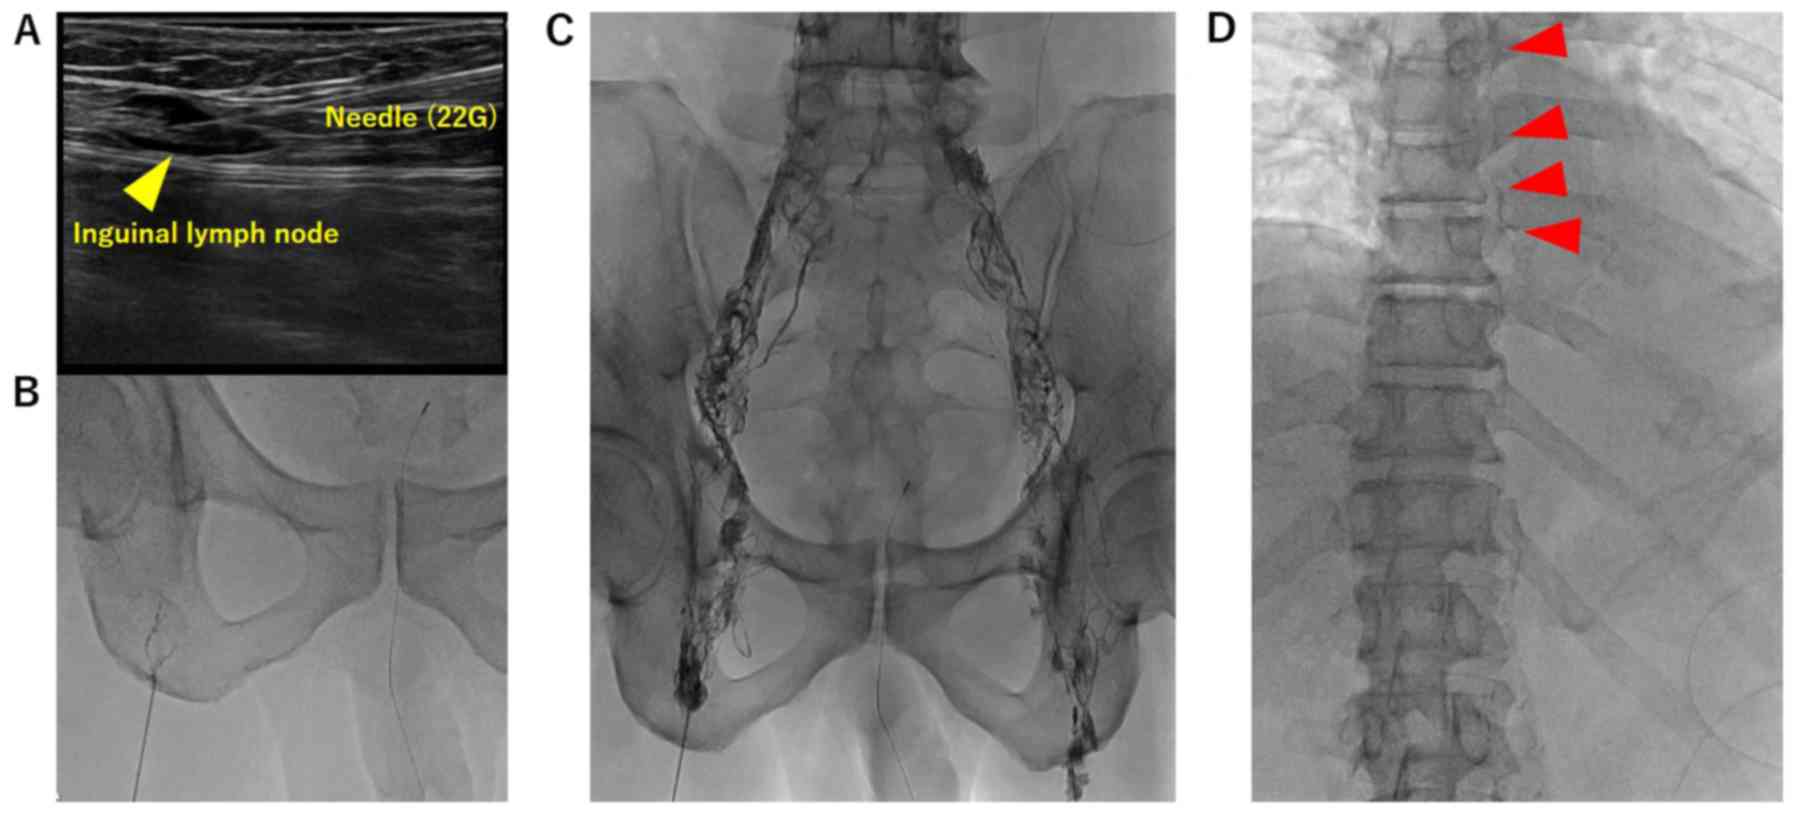

Figure 1.

Representative images of the procedure in case 1. (A) Puncture of both sides of the inguinal lymph nodes (yellow arrowhead). (B) Injection of Lipiodol (1 ml over 3 min) and detection of the lymphatic duct. (C) Contrast injection to visualize the lymph nodes around the common iliac vessels and the para-aortic lymph nodes. (D) Visualization of the thoracic duct (red arrowheads).

A 67-year-old man was diagnosed as having middle thoracic esophageal squamous cell carcinoma of cT3N1M0 cStage IIIA (UICC 8th edition). He underwent radical esophagectomy by video-assisted thoracic surgery (VATS) following 2 cycles of neoadjuvant biweekly-DCF chemotherapy (docetaxel 35 mg/m2 on days 1 and 15; cisplatin 40 mg/m2 on days 1 and 15; and 5-FU 400 mg/m2/day on days 1-5 and 15-19; Bi-DCF). Operation time was 515 min, blood loss was 145 g, and the thoracic duct was preserved. After enteral feeding was started on postoperative day (POD) 2, right pleural effusion drainage increased to 1,360 ml daily and changed to a milky white color. The patient then was diagnosed as having postoperative chylothorax. After conservative treatment including fat restriction was started on the same day, the chylothorax improved for a few days. However, he complained of breathing difficulties after enteral nutrition that included added fat. Re-exacerbation of the chylothorax up to 1,500 ml daily was observed on POD 15, and conservative treatment was started once again. On POD 50, ultrasound-guided intranodal Lipiodol lymphangiography involving inguinal lymph node puncture (Fig. 1) was performed that revealed Lipiodol leakage 4 cm on the caudal side of the tracheal bifurcation along the thoracic duct (Fig. 2A). Ligation of the thoracic duct by VATS was performed following the lymphangiography. Thoracic duct was identified in the lower mediastinum, and clipping was performed on the caudal side of the injured part (Fig. 2A). The patient's chylothorax improved completely by the next day, and the right thoracic drain was removed 7 days after the operation (Fig. 2C).